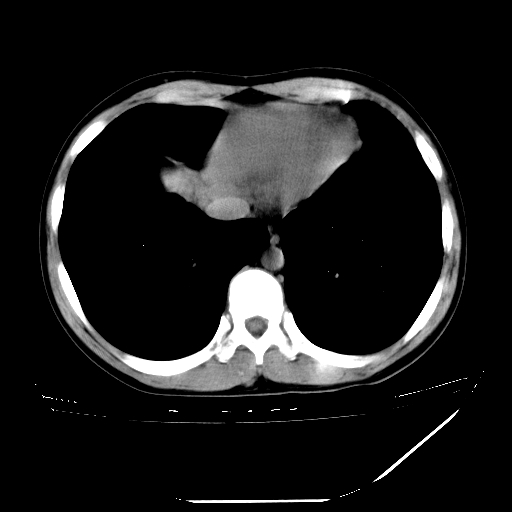

男,13岁,咳嗽、咳痰伴发热一周。

中上纵隔见多枚淋巴结肿大,部分相互融合成团片,左肺门增大,上叶支气管变窄,肺内多处斑片状 索条状及棉絮状致密影。临床“男,13岁,咳嗽、咳痰伴发热一周。”首先考虑:原发综合征!不除外淋巴瘤可能!

纵隔多发肿大淋巴结,部份有融合改变。双肺血管气管束增厚,以肺门为中心向外周散发,以左肺下叶为明显。考虑淋巴瘤可能性大。不除外原发综合征。

中上纵隔见多枚淋巴结肿大,部分相互融合成团片,左肺门增大,上叶支气管变窄,左肺支气管血管束增粗,可见磨玻璃样影。临床“男,13岁,咳嗽、咳痰伴发热一周。”首先考虑:淋巴瘤可能性大!

中上纵隔见多枚淋巴结肿大,部分相互融合成团片,纵隔内脂肪间隙模糊,左肺门增大,上叶支气管变窄,左肺支气管血管束增粗,可见磨玻璃样影。考虑纵隔淋巴管炎